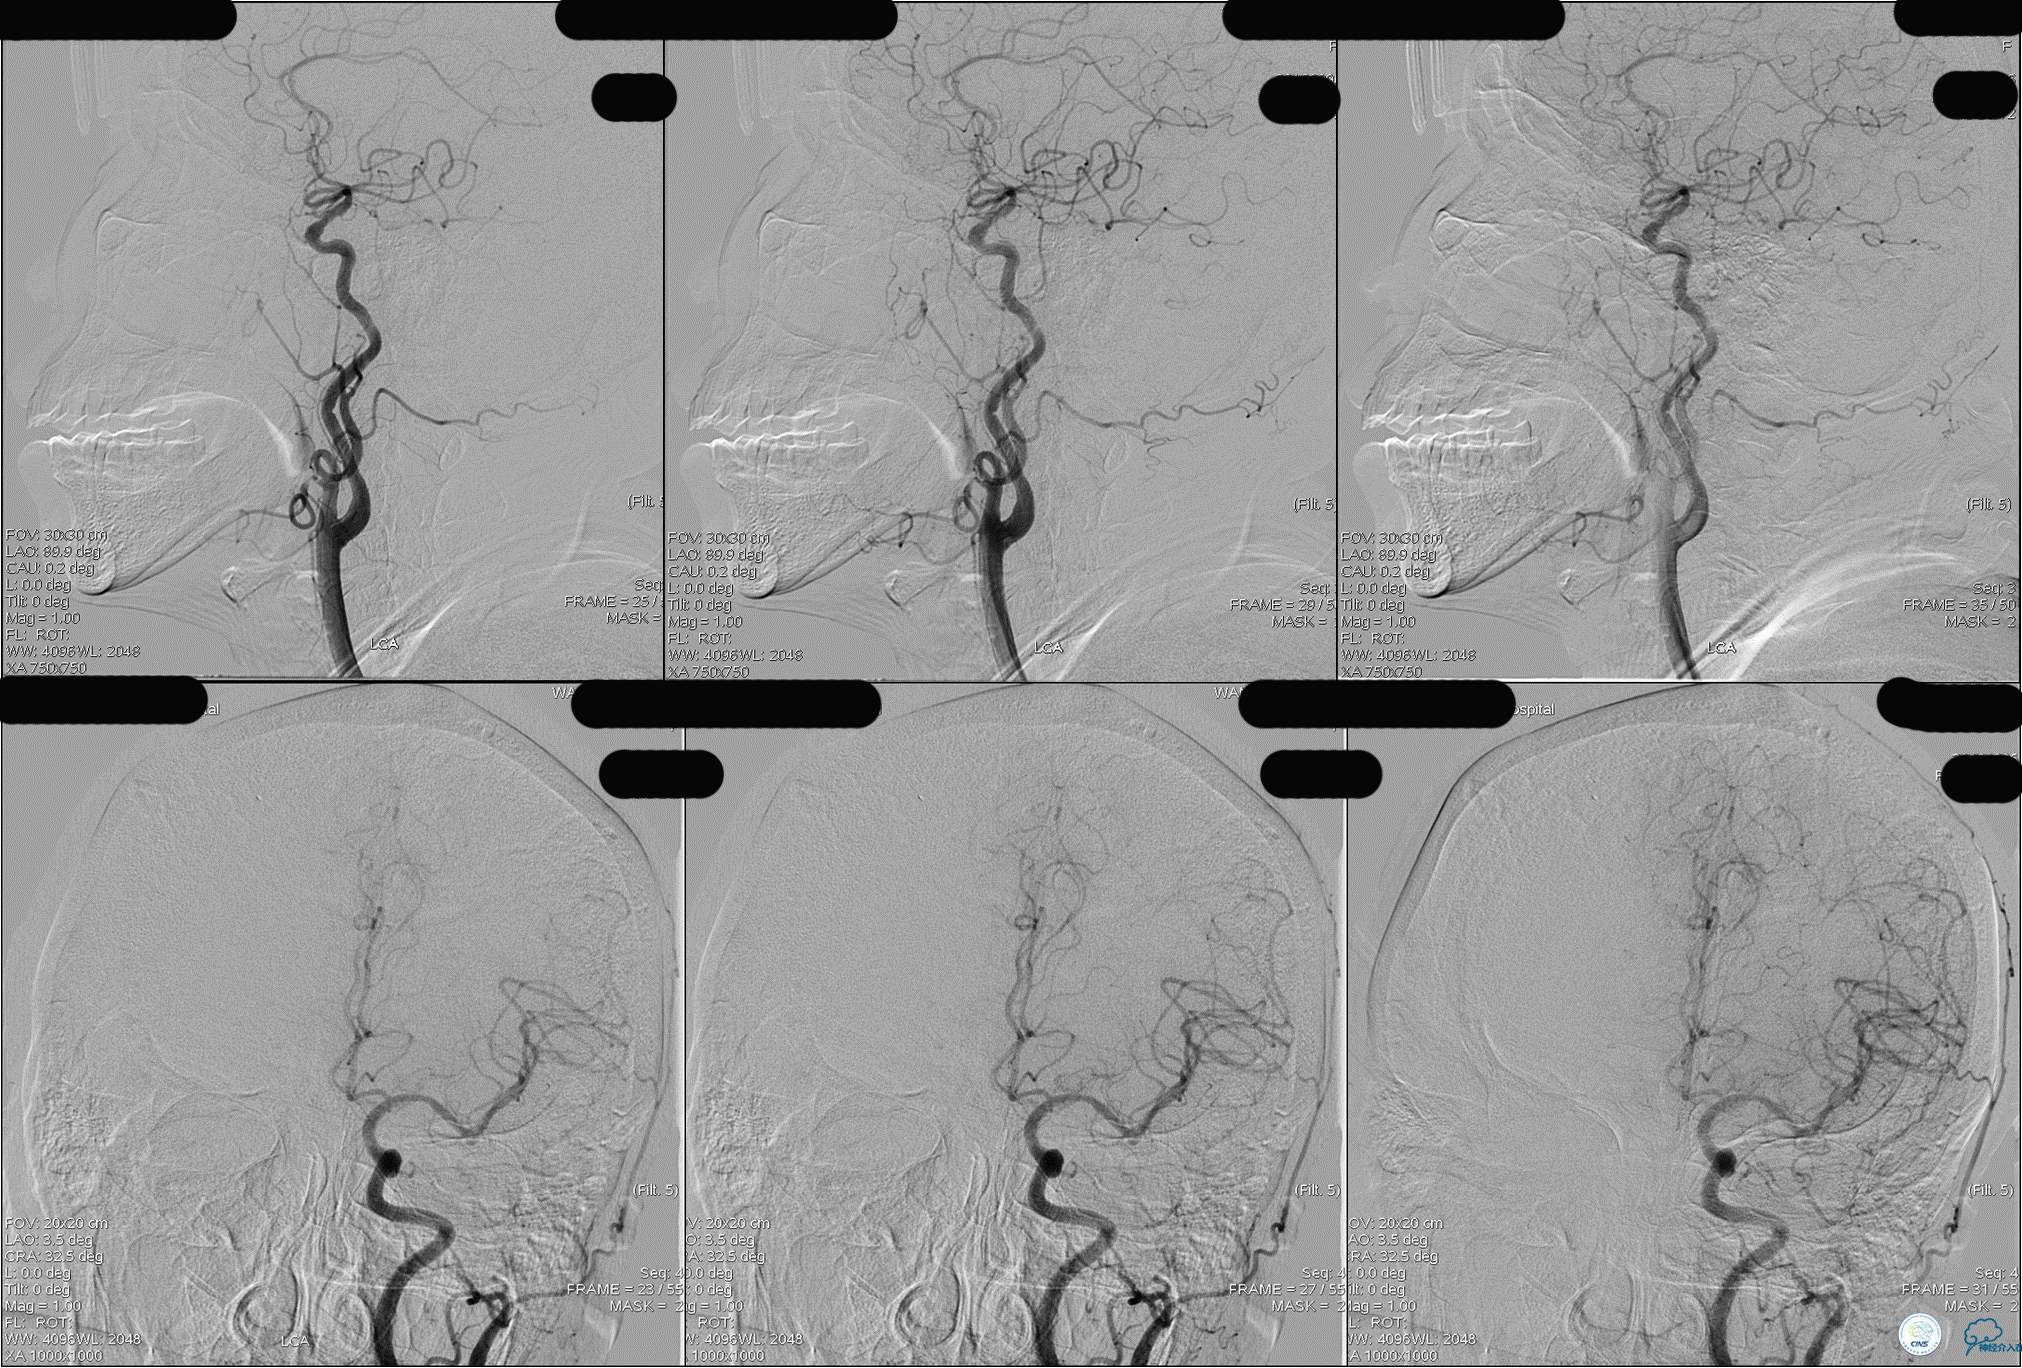

》DSA资料(左侧颈动脉)

》DSA资料(右侧颈动脉)

》DSA资料(左侧椎动脉)

》DSA资料(右侧椎动脉)